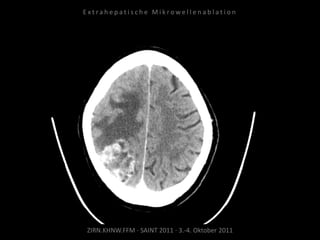

Verlaufskontrolle:

CT 04.08.2011

Lungenmetastase deutlich progredient.

Neu diagnostizierte Hirnmetastase.